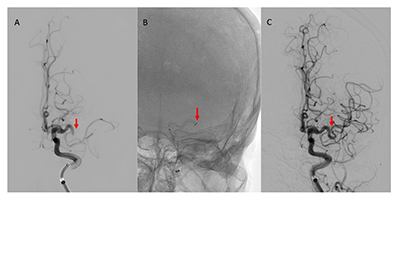

Results: Of 141 MT cases, 132 were included (mean age 64.2 years; 87.8% Thai). Anterior circulation strokes accounted for 87.9%. Successful reperfusion (mTICI ≥2b) occurred in 81.1%, and functional independence at 90 days in 70.5%. Lower baseline NIHSS showed borderline association with functional independence (p=0.059). Post-procedural aICH or no ICH significantly reduced odds of functional independence compared with sICH (aICH: OR 0.09, 95% CI 0.02-0.45, p=0.006; no ICH: OR 0.05, 95% CI 0.01-0.20, p<0.001). Age, sex, atrial fibrillation, onset-to-recanalization time, and first-pass success were not significant predictors. sICH was more frequent with IVT+MT than MT alone (17.4% vs. 1.6%, p=0.006).